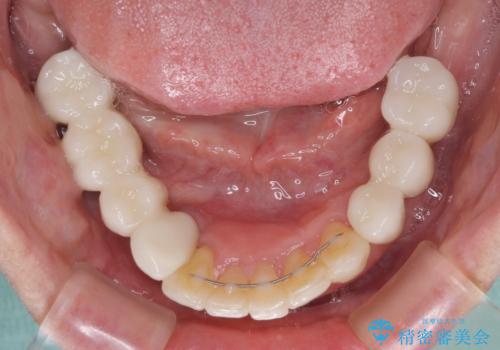

- 歯周病を放置したことで奥歯が抜け、前歯も痛くなってきたとのことで来院された患者様です。

奥歯はほとんどを抜歯しなければならない状態であり、抜歯をせずに済む歯も歯周外科処置や矯正治療を行う必要がある状態でした。

歯を抜かないといけない部分はインプラントとオールセラミッククラウンにより咬合を回復させ、歯周外科処置を行う歯については、同じくオールセラミッククラウンにて補綴治療を行うこととしました。

外科処置を多く行ったため、その待ち時間が長くかかり、さらには途中矯正治療も行なったので、治療期間は長期間となりました。